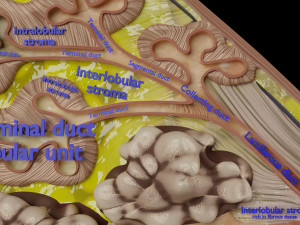

This is a 1:1 scaled model of right breast cut opened in sagittal plane to reveal its internal antomy and histology (schematic). The deeper parts and fascial layers are also depicted to give a very detailed approach to the model. The full layers starting from skin, nipple areola, till intercodtal muscles and ribs are also depicted.

breast mammary gland female chest wall anatomy human medical science reproductive genitalia muscle fascia milk nipple areola subcutaneous fatДо даного товару немає коментарів.